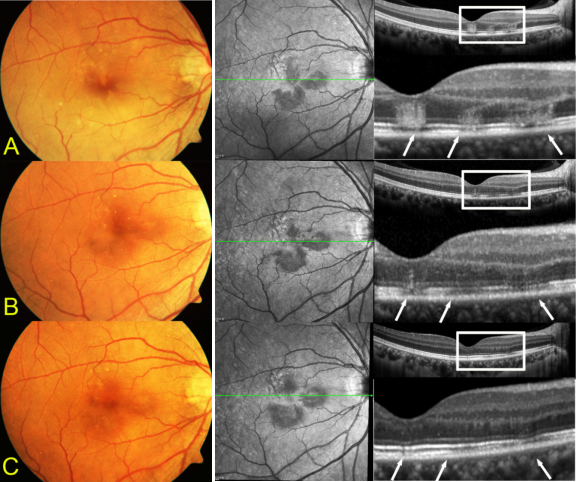

息肉状脉络膜血管病变( poly poidal choroidal vasculopathy, PCV)在20多年前国内鲜有人知,笔者通过吲哚菁绿血管造影(indocyanine green angiography, ICGA)陆续在部分眼底出血量较多的年龄相关性黄斑变性(age-related macular degeneration, AMD)患者中发现影像异常,积累病例后分析认为这部分患眼ICGA早期中有令人印象深刻的特征性囊袋样强荧光,通过文献检索发现国外已有学者将这类疾病命名为PCV。笔者在2001年第九届全国眼底病年会上在国内首次报道15只国人PCV患眼的临床特征(图2),引起广泛关注,此后通过国内不断的学术宣讲向临床眼科医生普及PCV知识。也自此开展团队对PCV的不断思辨创新和探索研究,涉及PCV的人口学特点、发病比例、基因易感性、临床影像学分析、合并症、治疗和预后等诸多领域,2014年获评我国眼底病近5年十大研究进展之一。2004年团队报道了国人新生血管性AMD中PCV的比例为22%[1]。经过多年对PCV的认识加深和多模式眼底影像工具用于PCV诊断,2022年团队更新国人湿性AMD中PCV的比例为58%[2],PCV发病比例成为国人新生血管性AMD亚型中第一位,足见PCV领域研究对眼底病防治的重要性。

图 2 笔者在国内报道的第一例息肉状脉络膜血管病变

Figure 2 The first reported case of polypoidal choroidal vasculopathy in China